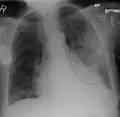

Normal lateral CXR -

AP CXR showing pneumonia of the lingula of the left lung -

Right upper lobe pneumonia as marked by the circle. -

Left upper lobe pneumonia with a small pleural effusion.